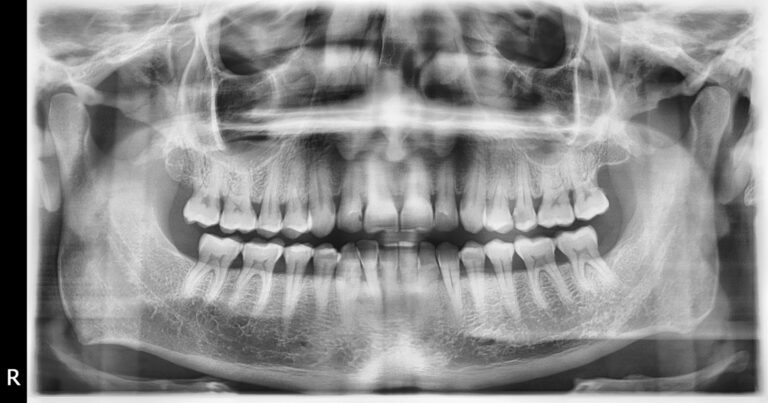

WHAT IS A DVT RECORDING? DVT stands for Dental Volumetric Tomography and is the latest generation of 3D CT devices….